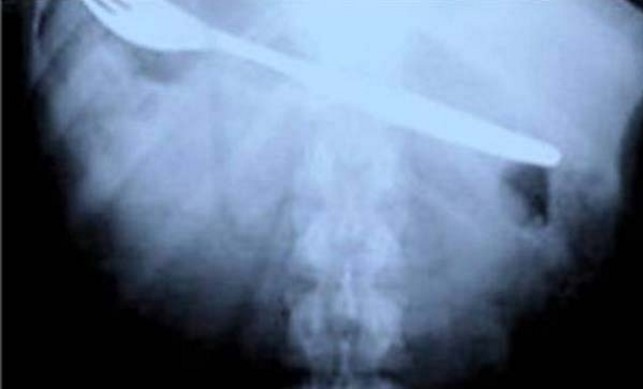

3. Garpu.